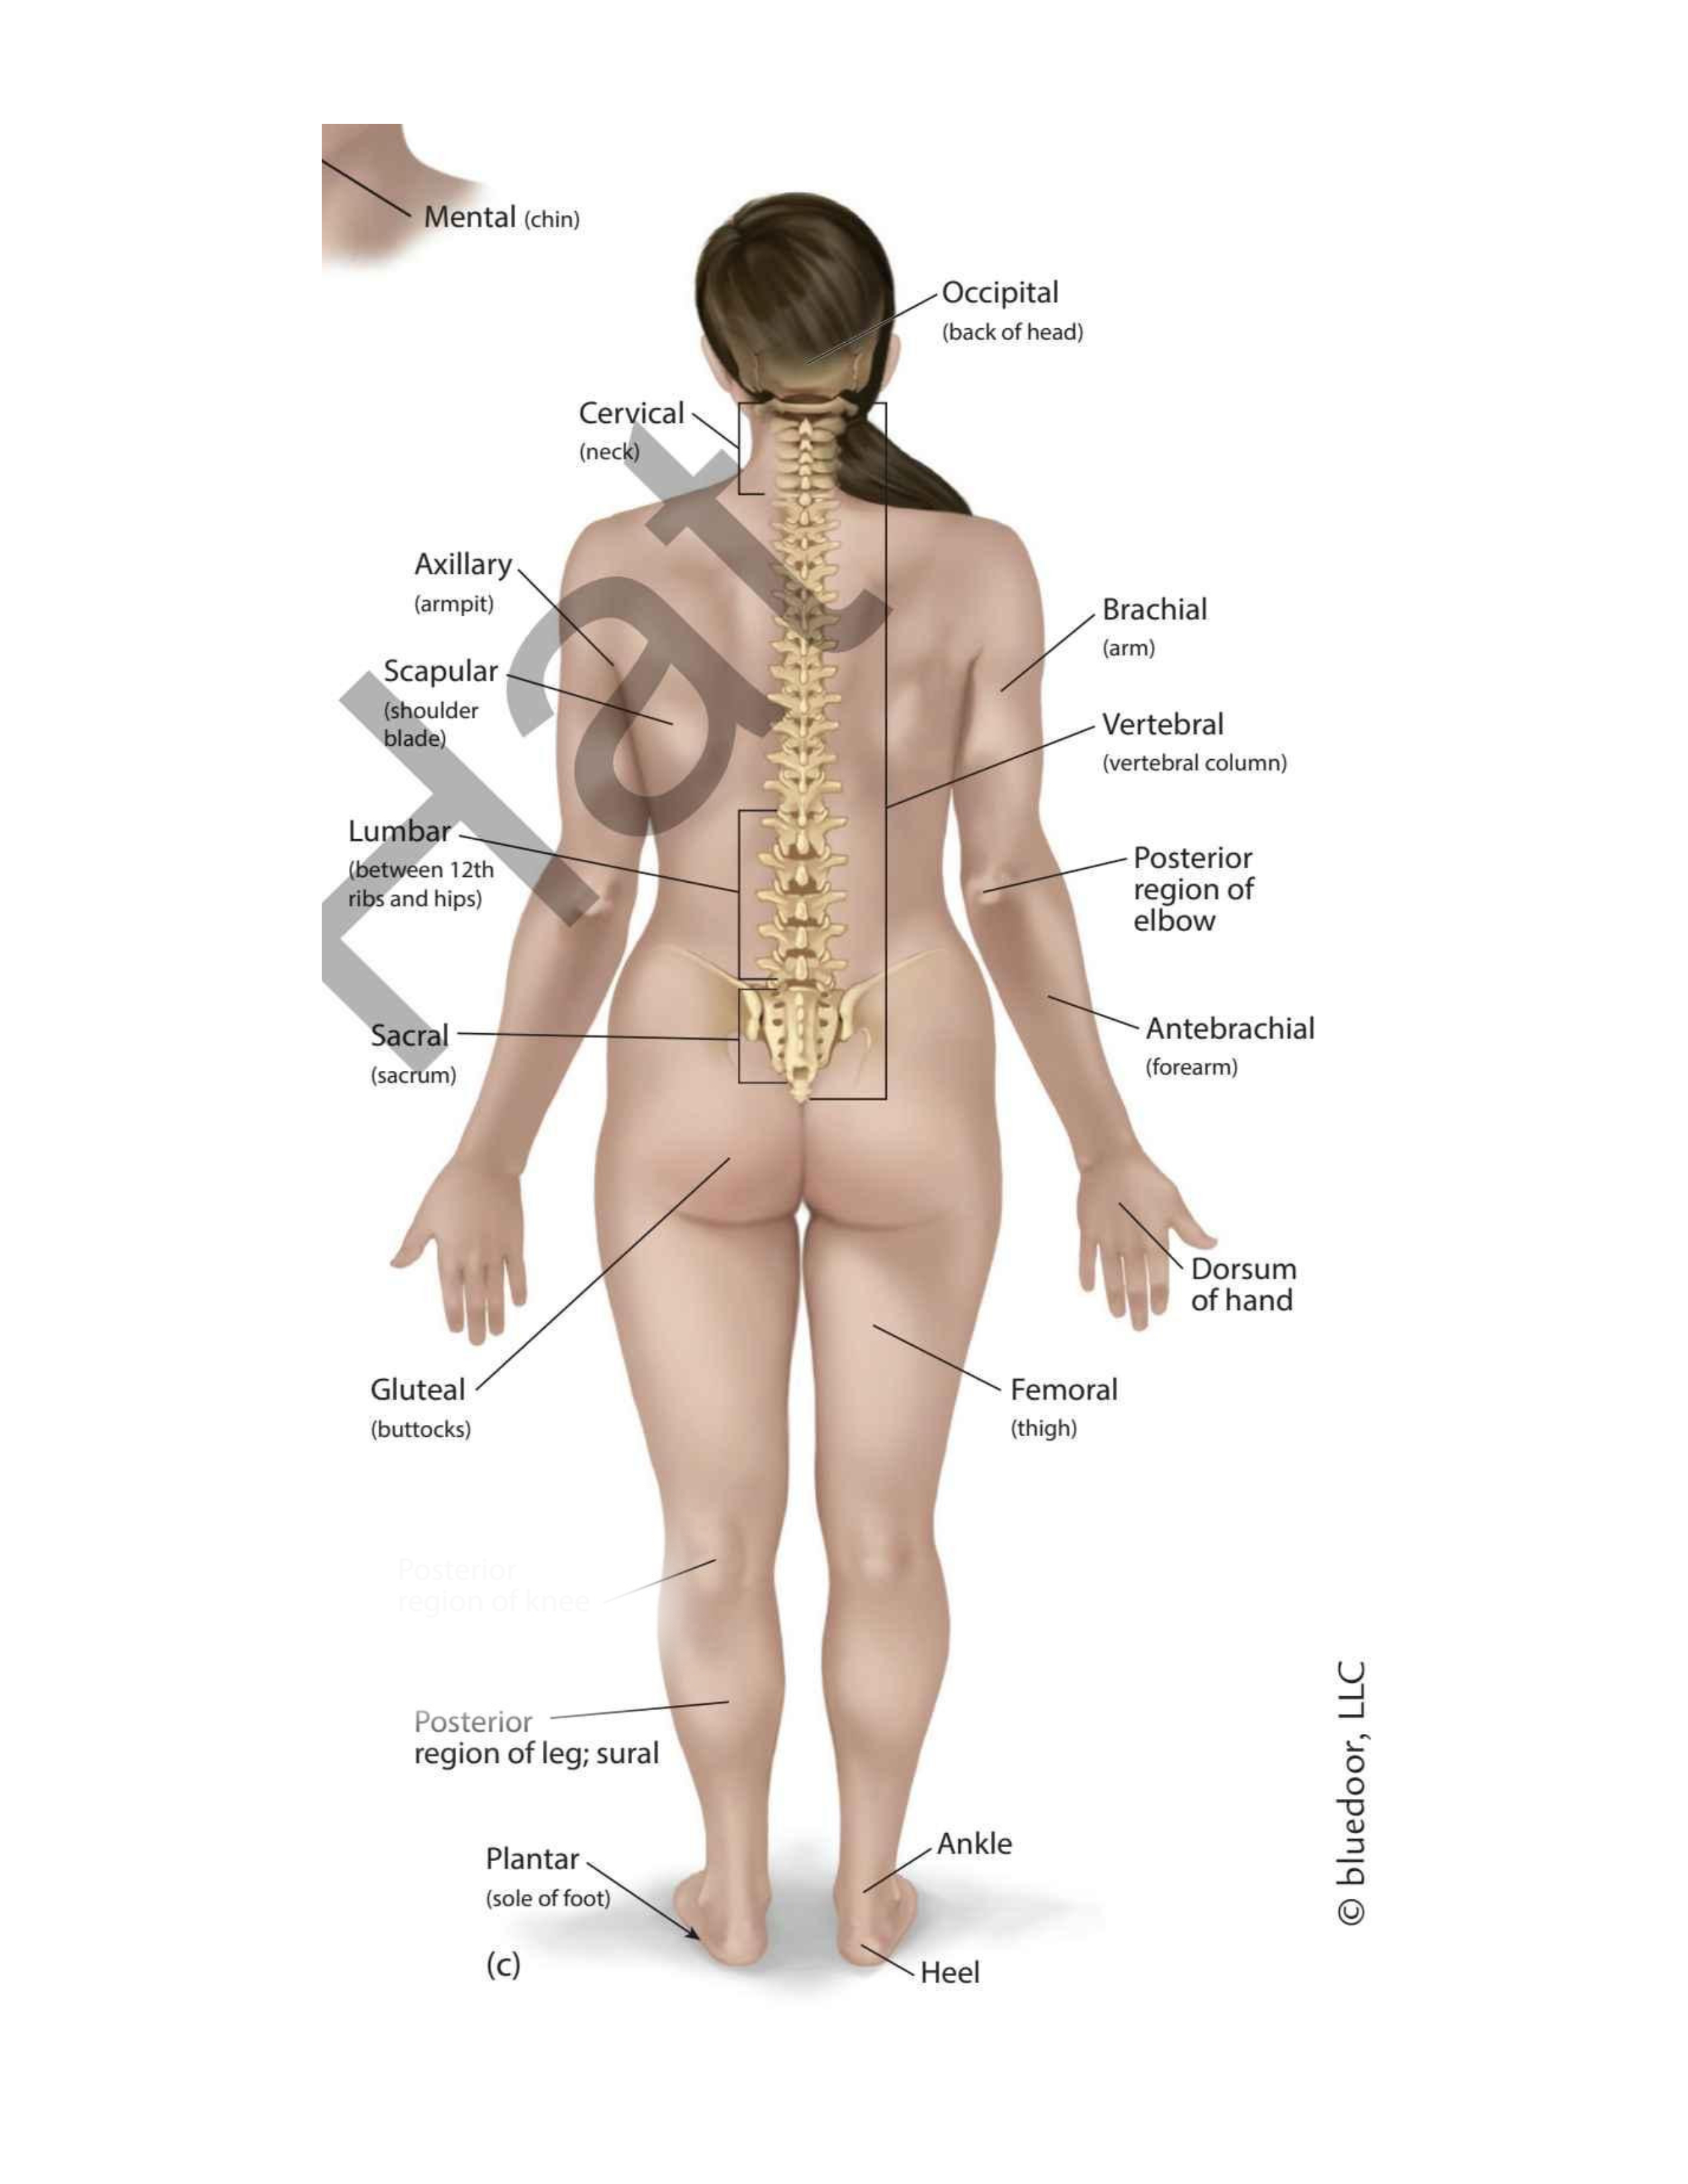

(forehead)

Frontal

(chin)

Mental

(wrist)

Carpal

(thigh)

Femoral

(elbow)

Antecubital

(back elbow)

Olecranal

(back knee)

Popliteal

(heel)

Calcaneal

(shoulder blades)

Scapular

(sole)

Plantar